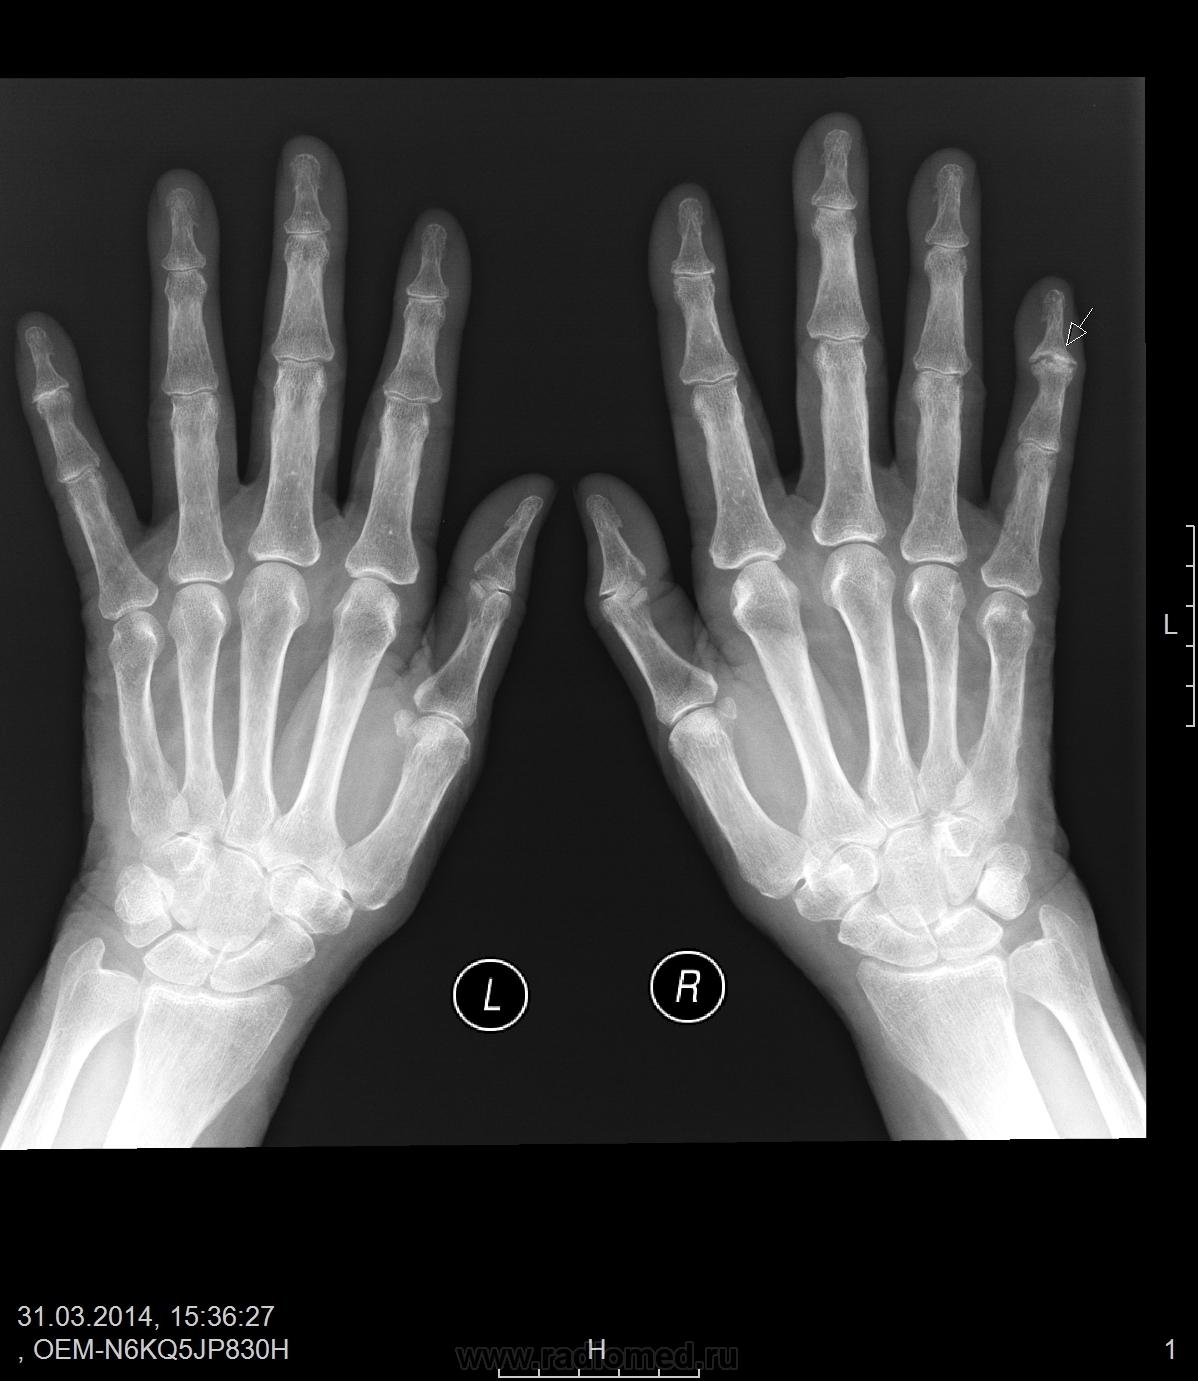

Артроз м/ф сустава V пальца справа

Считаю, что артрит (ну или последствия артрита). Узурация суставных поверхностей есть. Анамнез бы - не было ли в прошлом или настоящем симптомов артрита

Из анамнеза: суставной синдром - 1год. Из аналзиов: РФ-250, СРБ - 15.  Тобишь Рг картина расширения суставной щели и узурация суставной поверхности. А такое выборочное поражение для чего характерно?

О расширении суставной щели можно говорить в случаях наличия в суставе выпота - в крупных суставах, и то не факт, как пишет уважаемый Самуил Аронович, здесь она ассиметрична, сужена, кажущееся расширение обусловлено узурацией. Вот насчёт нозологии я вам не подскажу, пусть ревматологи оценивают. Указанные вами лабораторные показатели намного ведь выше нормы - тогда однозначно к ревматологам

Из разговора бабушек на скамейке во дворе: "Вот уж как год как взялись руки болеть, никакого спасу не дают". -"Да это у тебя, Патрикеевна, подагра." В данном случае я с ними согласен - псевдоподагра (хондрокальциноз). А снимки очень качественные.

а если приглядеться повнимательней (снимки это позволяют) можно выявить признаки патологии в каждом суставе, и поставить диагноз полиартрит. А уж какой он этилогии это нужно терапевту покопаться. Я лично  склоняюсь к мысли что все таки подагра.

тоже, думаю, что это подагрический артрит, для уточнения диагноза, рекомендовала бы еще, помимо лабораторных анализов, рентгенографию обеих стоп.